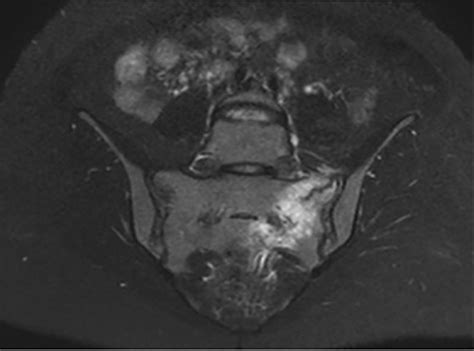

Mri is the radiological examination of choice by some doctors. Sacral insufficiency fractures are a subtype of stress fractures, which are the result of normal stresses on abnormal bone, most frequently seen in the setting of osteoporosis.

Prevalence is likely underestimated 1.

Mri is being utilized more routinely in the evaluation of patients with lower back and pelvic. Insufficiency fractures of the sacrum can be a cause of lumbosacral pain in patients after pelvic cancer radiotherapy. The combination of low bone density and increased activity blurs the boundary between fatigue and insufficiency fractures in many runners. Since then, there has been much more cases reported due to the awareness of this entity, however, there is often a delay in diagnosis because clinical symptoms are. 10 other sites frequently affected by insufficiency fractures are the thoracic vertebra, tibia, fibula, and calcaneus. Most patients have delay in the diagnosis of sacral fracture as the symptoms can be more vague. Prevalence is likely underestimated 1. Insufficiency fractures of the sacrum are not uncommon and usually occur in osteoporotic bone with minimal or unremembered trauma. Mri is being utilized more routinely in the evaluation of patients with lower back and pelvic. Sacral insufficiency fractures (sif) are a commonly misdiagnosed painful condition in patients with osteoporosis. Symptoms included lower back or buttock pain, abdominal pain, and purpose. Sacral insufficiency fractures (sifs) result from normal stress applied to abnormal bone; Chapter 119 sacral insufficiency fractures. Insufficiency fractures of the sacrum are an underrecognized cause of low back pain, particularly in the elderly female. 1 sacral insufficiency fracture with a horizontal component through s2. Sacral insufficiency fractures usually are parallel to the spine. Ct may have trouble in demonstrating fractures in the plane of the image (transverse protect patient from possible sacral decubiti.